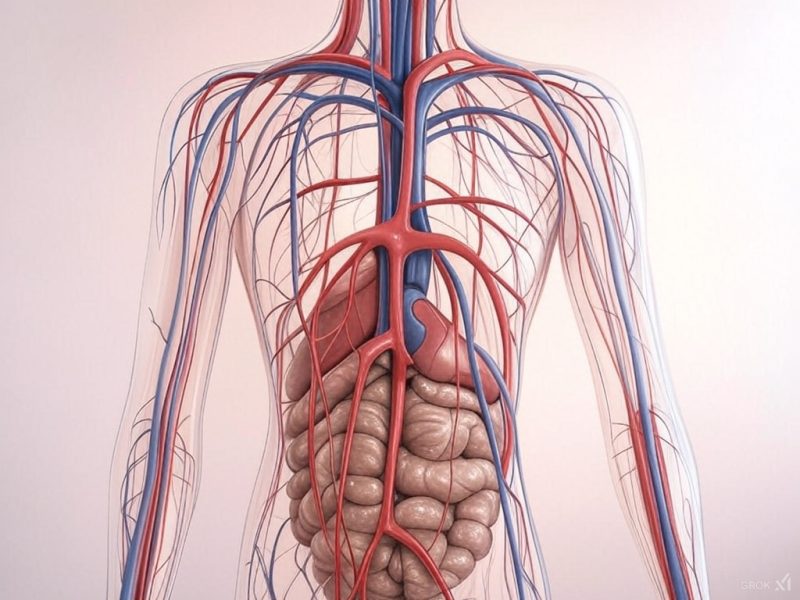

في إنجاز طبي غير مسبوق، نجح فريق طبي وتمريضي متخصص بالمركز الاستشفائي مولاي يوسف بالرباط يوم الثلاثاء 25 فبراير 2025، في إجراء أول عملية جراحية لعلاج قصور الصمام الثلاثي بالقلب وذلك بالمركز الاستشفائي مولاي يوسف بالرباط.

وأشرف على هذه العملية الجراحية المعقدة والتي دامت لقرابة 5 ساعات، البروفيسور محمد العروسي، رئيس قسم جراحة القلب بالمركز الاستشفائي الجامعي ابن سينا بالرباط، وذلك بالتعاون مع فريق طبي وتمريضي من المركز الاستشفائي مولاي يوسف. وأجريت لمريض يبلغ من العمر 63 عامًا، وكانت تتطلب درجة عالية من الدقة والتركيز بسبب طبيعتها المعقدة.

ويعتبر هذا الإنجاز الطبي الأول من نوعه، علامة فارقة في مجال جراحة القلب والشرايين بالمغرب، حيث يتم إجراء مثل هذه العمليات عادة في المراكز الاستشفائية الجامعية المتخصصة، كما أن نجاح العملية يؤكد على الكفاءة العالية للطاقم الطبي والتمريضي المغربي، وقدرته على التعامل مع الحالات الطبية المعقدة بأعلى معايير الجودة.

كما يُظهر هذا الإنجاز الطبي الإمكانيات المتقدمة التي يتوفر عليها المركز الاستشفائي مولاي يوسف، مما يعزز مكانته كواحد من أهم المراكز الطبية في المغرب وقطبا للتميز في مجال طب القلب والشرايين، كما يؤكد نجاح العملية على التطور الكبير الذي تشهده الخدمات الصحية العمومية في البلاد، وقدرتها على تقديم رعاية طبية عالية الجودة تلبي احتياجات المواطنين.